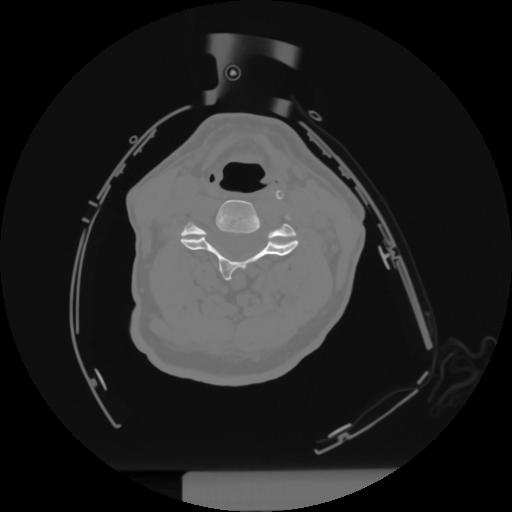

12 P.BLANDAS,,Vol,0.5,P.BLANDAS,,